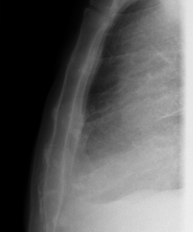

- RX Tòrax

Tècnica que usa els raigs X a través de la qual s'obtenen imatges de la caixa toràcica (cor, pulmó, arcs costal, clavícules, etc.) per al seu estudi. - RX Ester

Tècnica que usa els raigs X a través de la qual s'obtenen imatges de les costelles per al seu estudi. - RX Columna dorsal